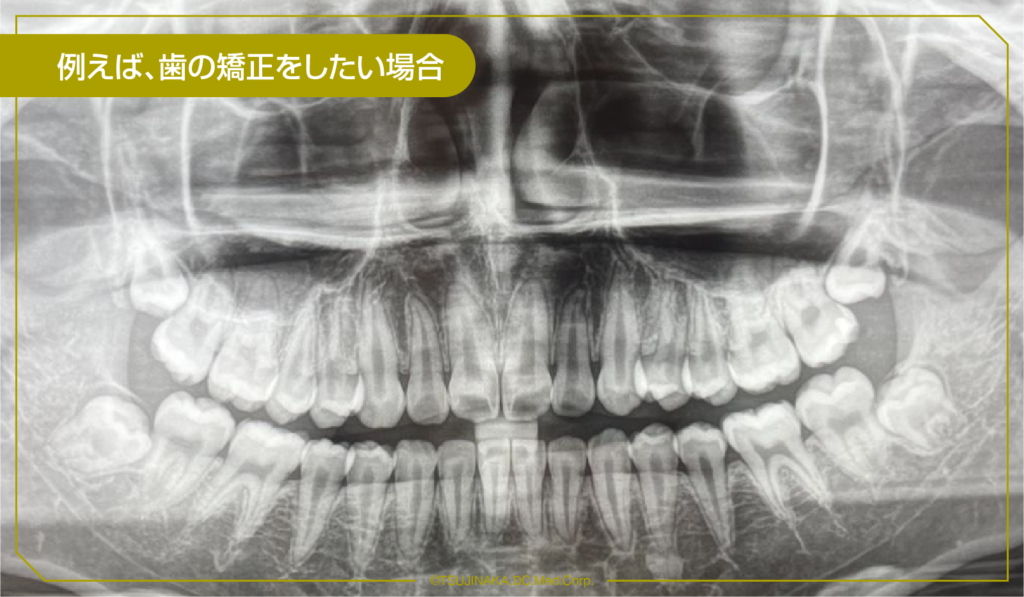

例えば、歯の矯正をしたい場合

矯正診断をする上で大切な資料(精密検査)を集めます。

・お顔の写真(正面と側方)や口腔内写真(いつも噛み合わせている位置で正面、側方、上顎、下顎)の計5枚

・パノラマX線写真(歯の萌出状態や欠如している歯だったり歯の根っこの状態を確認する為)

・頭部の発育状態や不正咬合の状態を調べる頭部X線規格写真(セファログラム)などこのような資料集めをします。

その後先生からの診断を受け、治療に進む流れになっております。